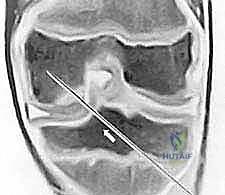

- الأشعة السينية (X-Rays): تُعد الخطوة الأولى لاستبعاد الكسور وتقييم الهيكل العظمي العام، وغالباً ما تُظهر الآفة في المراحل المتقدمة.

- التصوير بالرنين المغناطيسي (MRI): هو "المعيار الذهبي" للتشخيص. بفضل خبرة الدكتور هطيف العميقة، يتم تحليل صور الرنين لتقييم صحة الغضروف، مدى انفصال القطعة العظمية، وحالة الأربطة المحيطة. الرنين يحدد ما إذا كانت الآفة مستقرة (يمكن علاجها بدون جراحة) أو غير مستقرة (تتطلب تدخلاً جراحياً).

- الأشعة المقطعية (CT Scan): قد تُطلب في حالات خاصة لتحديد حجم العظم المفقود بدقة ثلاثية الأبعاد قبل التخطيط للجراحة.